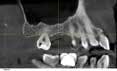

Case 2: Lateral wall sinus osteotomy with block grafting and platelet-rich fibrin (PRF)

An 81-year-old female with stent placement 10 years ago taking no medications presented with a chief complaint that her old prosthesis broke, and she cannot chew and function. She had a previous bridge consisting of an implant in the No. 1 site combined with the natural teeth and implants in the 8, 9, 14, 15. No. 8, 9 implants were malpositioned with a 35-degree angle and significant mucogingival defects.

Various treatment options were explained to the patient, and a treatment plan consisting of Coldwell-Luc external sinus lift with bilateral block placement in area 5 to 7 and 10 to 12 was agreed upon.

Under local anesthesia, a full thickness flap was elevated from the upper right to upper left posterior segments. Using a piezoelectric handpiece, a buccal window hinge osteotomy was elevated in the maxillary right posterior region. A mixture of DFDBA, anorganic bovine bone, and PRF was placed. A collagen membrane was used to cover the buccal window. Simultaneously, two puros J-block allografts were secured in the 5 to 7 and 10 to 12 region with stainless steel screws (1.6 x 8 mm screws). A mixture of DFDBA, anorganic bovine bone and PRF was placed over each area and covered with PRF sheet and a collagen membrane. Primary closure was obtained with CV-5 Goretex sutures. Healing was uneventful. After six months of healing, six straight implants were placed in sites 3, 4, 5, 6, 11, and 12. Healing abutments were placed at stage I. Healing was uneventful. After four months of healing, six custom abutments were fabricated by his dentist and cover screws were placed on implants 8 and 9 and converted into pontics.

Case 2: Sinus lift, bone graft, PRP, and after healing implant placement